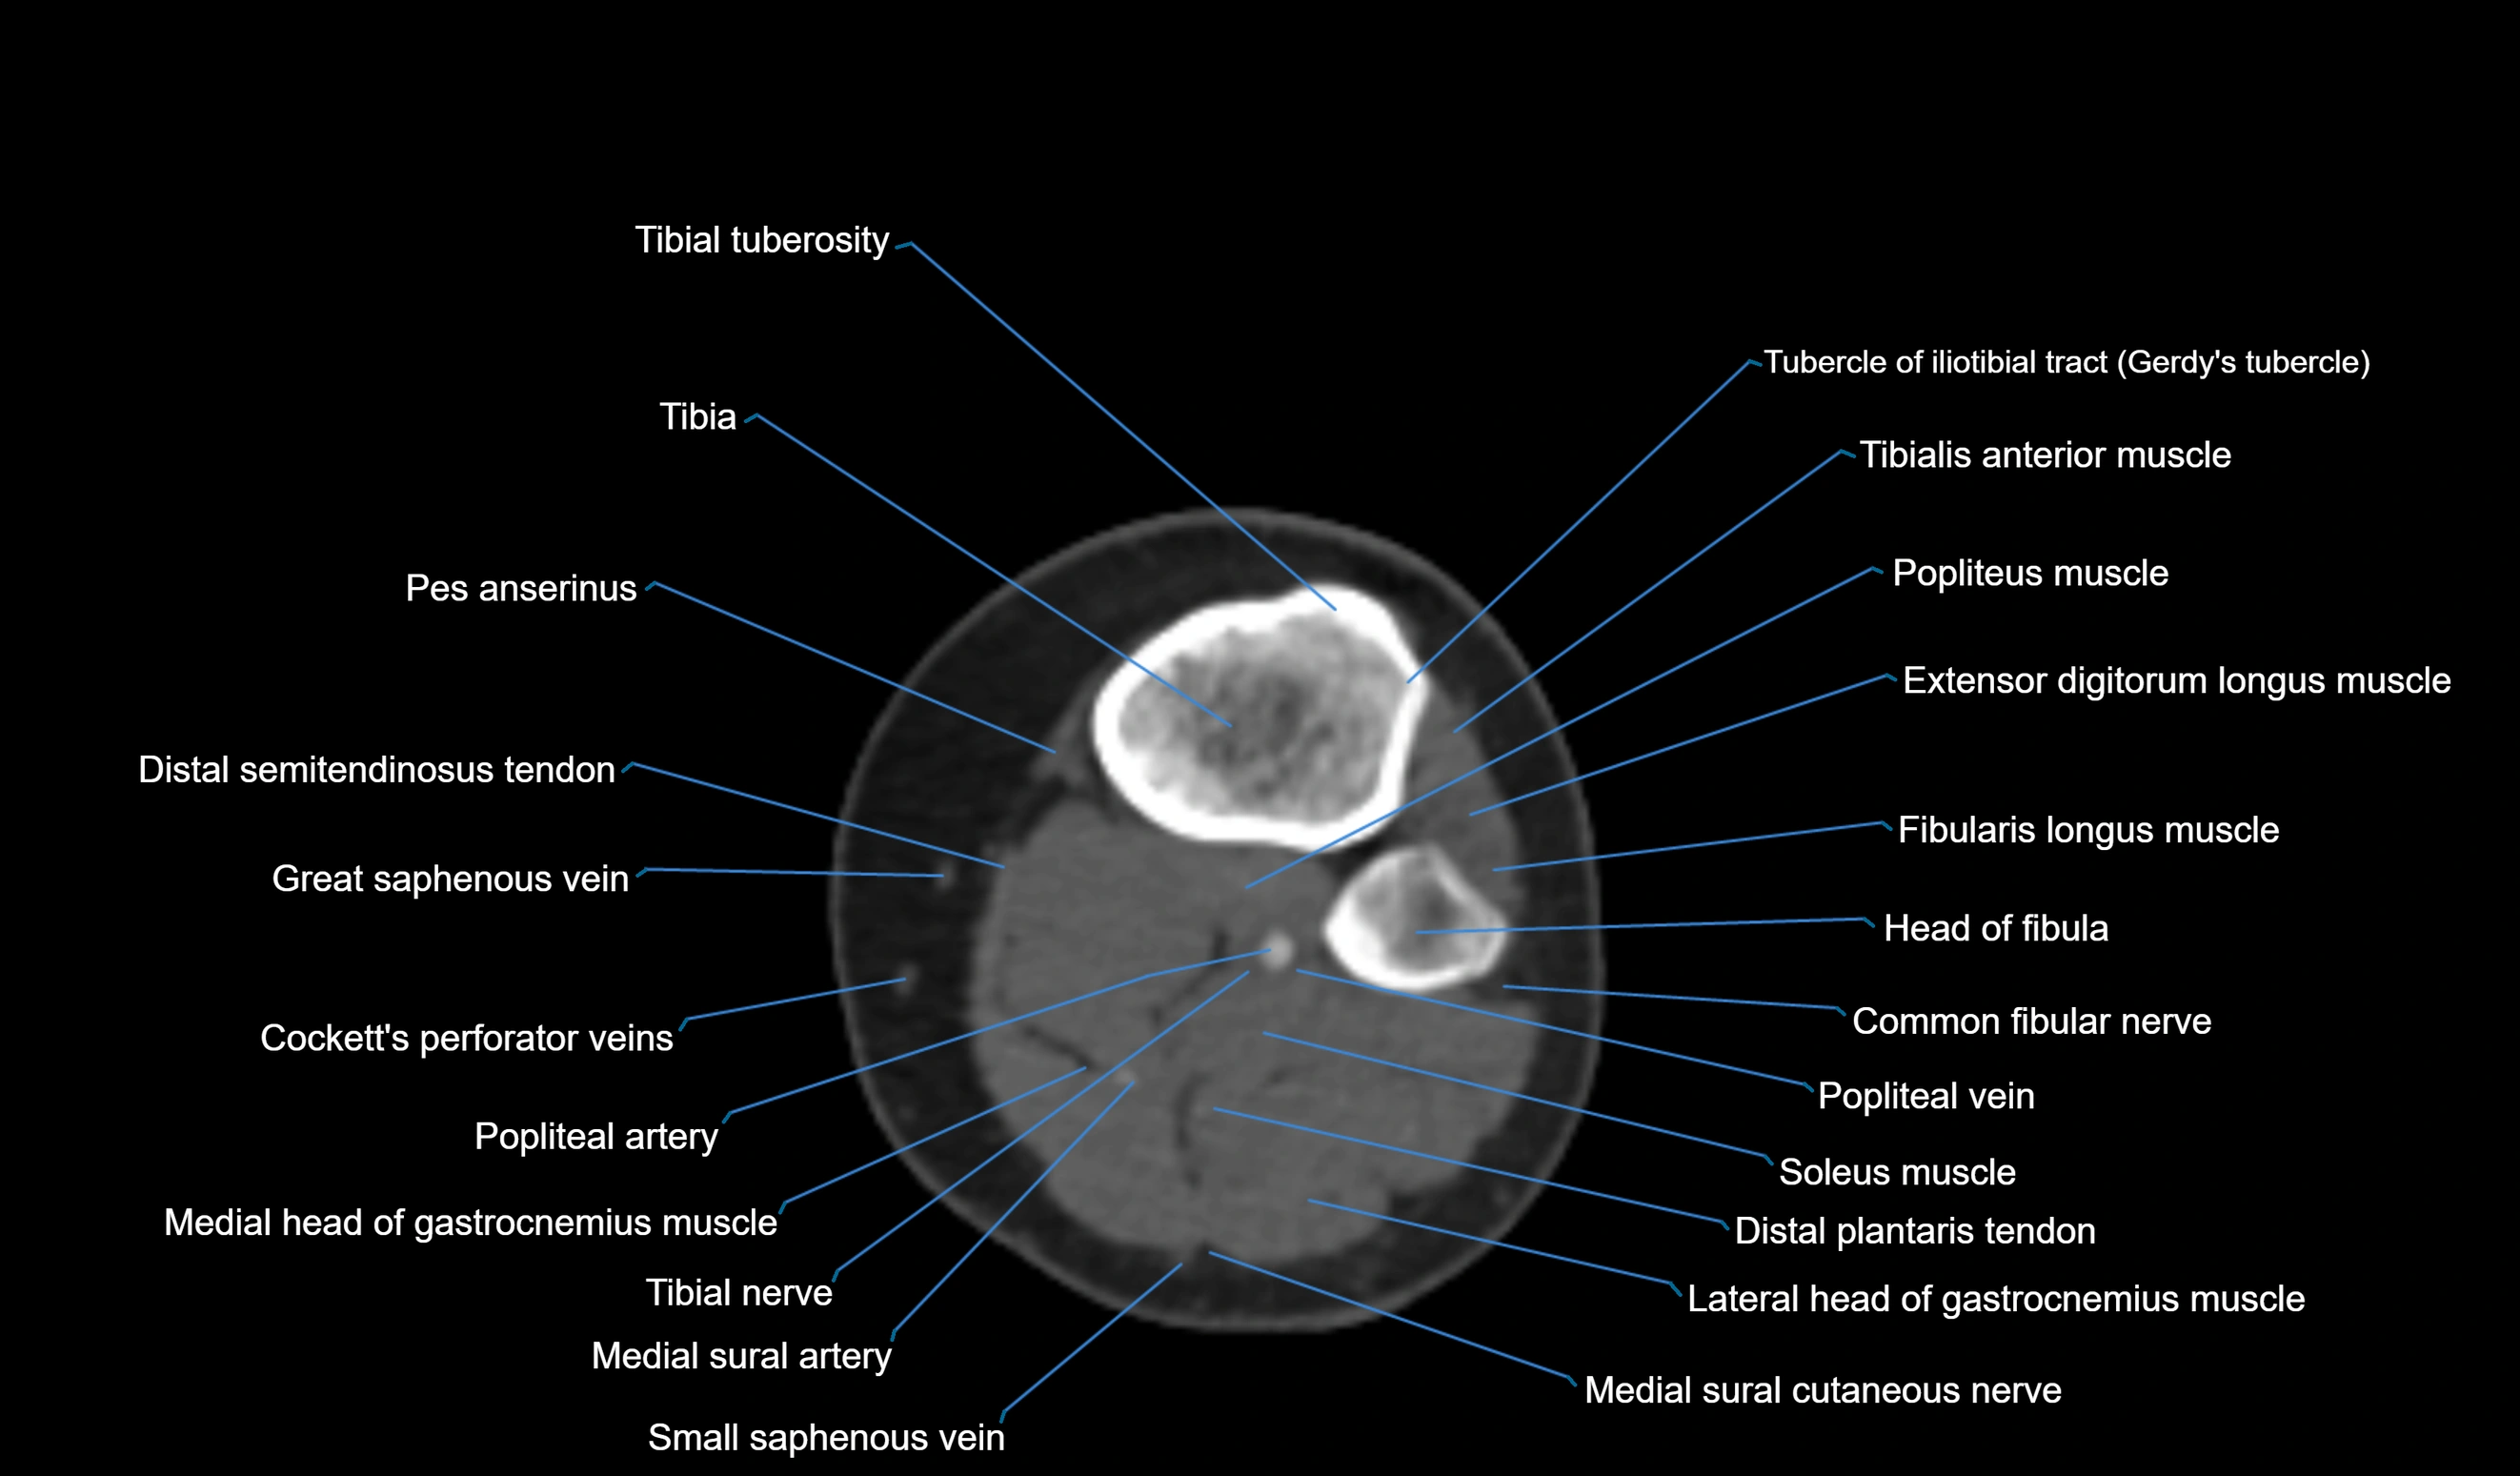

- Common fibular nerve

- Extensor digitorum longus muscle

- Fibularis longus muscle (peroneus longus muscle)

- Gerdy’s tubercle

- Head of fibula

- Lateral head of gastrocnemius muscle

- Medial head of gastrocnemius muscle

- Medial sural cutaneous nerve

- Popliteal artery

- Popliteal vein

- Small saphenous vein

- Soleus muscle

- Tibial tuberosity

- Tibialis anterior muscle

- Tibiofibular joint (proximal)